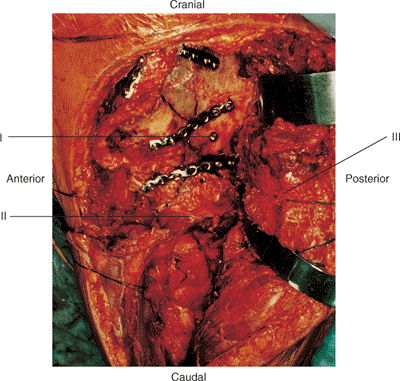

approach include (a) high (transtectal) transverse and T-type fracture

patterns with involvement of the weight bearing dome (Fig. 43.2);

Figure 43.1. The extended iliofemoral approach for exposure of a comminuted left both-column acetabular fracture. (i) Femoral head. (ii) Abductor muscles and tensor fascia lata. (iii) Schanz pin in greater trochanter parallel with femoral neck.

Figure 43.2. A 28-year-old man with right transtectal ischial T-type acetabular fracture. A. Preoperative AP pelvis. B. Postoperative AP pelvis.